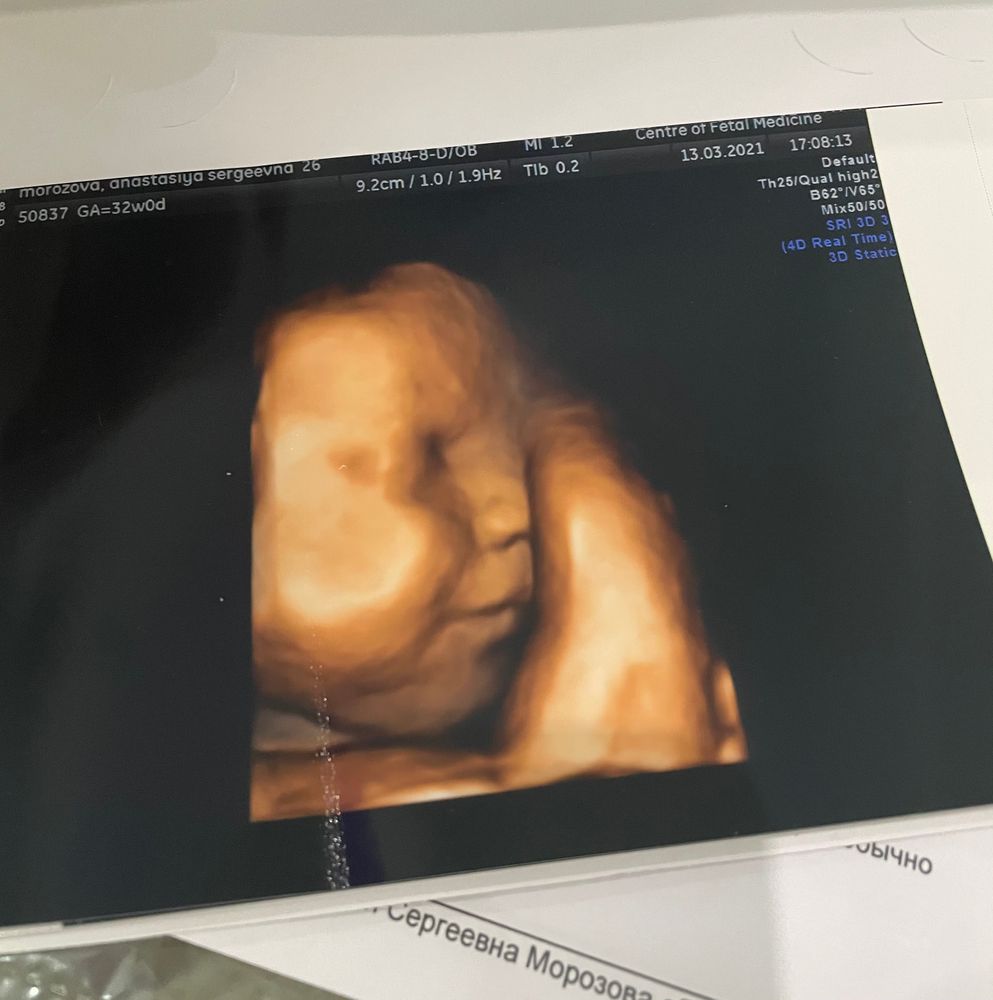

3 скрининг ✔️ 32 недели

Но! Этот Человек покорил моё сердце, а особенно то, что он улыбался 😍

Копия мужа и его младшего братика, от меня возможно только щеки 😅 а ещё мы крупненькие, сейчас весим 2150, на выходе подсчитали где-то 3800 и рост 54см 🙈 роды будут веселыми 👌🏻 Лежит правильно, обвития нет, зато есть трудовая мозоль на губе потому что кто-то активно сосет пальцы в животике 😊 а ещё сказали что родимся с шевелюрой, так как она уже огого какая 😅